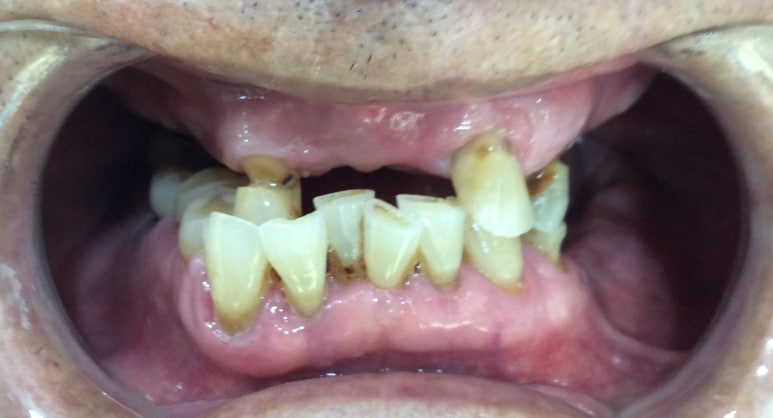

환자분이 사진공개에 동의한

실제 저희 치과에서 진행한

각종 몇가지 여러 임플란트, 틀니 케이스 공개해드립니다.

사진공개 동의하지 않은 케이스는 공개하지 않습니다.

- 기초 수급자 환자 흔들리는 위 치아 빼고 위 전체 틀니,

아래쪽 어금니는 씹을 수 있게 최소 개수의 임플란트